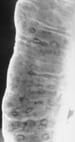

Results: Enteroscopy demonstrated a potential site of bleeding in 38 patients (69%), and 38% of lesions found were within the reach of the gastroscope. The most common lesions were small intestinal angiodysplasia. Seventy-five percent of patients with positive findings had alterations to their management. After subsequent treatment, 62% were no longer anemic and there was a significant reduction in rebleeding ( P < 0.05) and transfusion requirements ( P < 0.05) compared to patients with negative findings. The procedure was well tolerated and complications were rare.